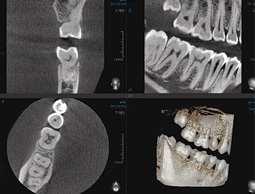

Dentale Volumentomographie

"3D-Computeraufnahme" in der Zahnmedizin

Das Spektrum für die Anwendung der Dentalen Volumentomographie (DVT) umfasst die Zahnheilkunde, insbesondere die Implantologie sowie die Mund-, Kiefer- und Gesichtschirurgie.

Anhand dieser Bilder kann Ihr Arzt noch detailliertere Diagnosen stellen und auch komplizierte Fragestellungen gezielt beantworten, z. B. perfekt angepassten Zahnersatz für Sie fertigen oder Ihre Implantatbehandlung millimetergenau planen.

Diese hochmoderne digitale Technik liefert hochaufgelöste 3D-Bilder bei geringster Strahlenbelastung.